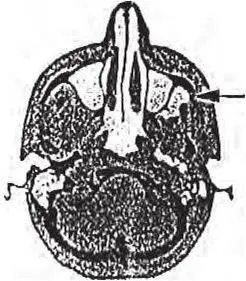

Рис. 2. Компьютерная томограмма: спустя 5 дней после анестезии на бугре верхней челюсти четко контурируется гематома в крылонебной ямке (указано стрелкой)

Однако необходимо помнить, что в процессе обезболивания при проведении анестезии на бугре верхней челюсти в результате повреждения инъекционной иглой вен крылонебного сплетения неизменно возникает гематома.

Проведенные нами компьютернотомографические исследования путей распространения инъецируемого анестетика при проведении «туберальной» анестезии подтвердили высокую вероятность такого осложнения.

На представленной компьютерной томограмме (рис. 2), произведенной спустя 5 дней после внутриротовой анестезии на бугре верхней челюсти, четко контурируется образовавшаяся гематома в крылонебной ямке. Вероятность ее нагнаивания и, следовательно, развития флегмоны этого клетчатного образования велика и достигает, по данным различных авторов и нашим наблюдениям, 40 – 60 % (Алехова Т. М., 1998; Бажанов Н. Н. [и др.], 1998; и др.).